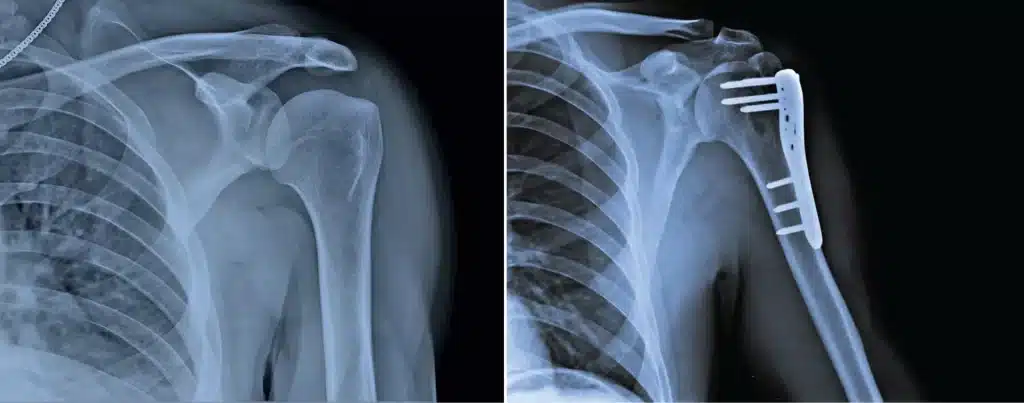

Shoulder (Proximal Humerus)

Shoulder fractures involve a fracture in the upper arm (humerus) near the shoulder, usually caused by falling on an outstretched hand.

geriatric shoulder fractures

If the fracture is not severe, non-surgical treatment with a sling or collar & cuff support for 6-8 weeks is sufficient to allow for adequate fracture healing. Physiotherapy and rehabilitation may be offered to restore function and prevent any shoulder stiffness.

fracture metalpins in the shoulder proximal hHumerus

If the fracture has multiple fragments or is severely displaced, surgery is often indicated. The type of surgery may vary, but in general, metal plates and screws will be inserted to hold the bone fragments stably in place. This will allow optimal healing and prevent deformities or disability in the fractured arm in the long run. For very severe fractures, a partial or total shoulder replacement is sometimes the best option to reliably restore shoulder movement and function.